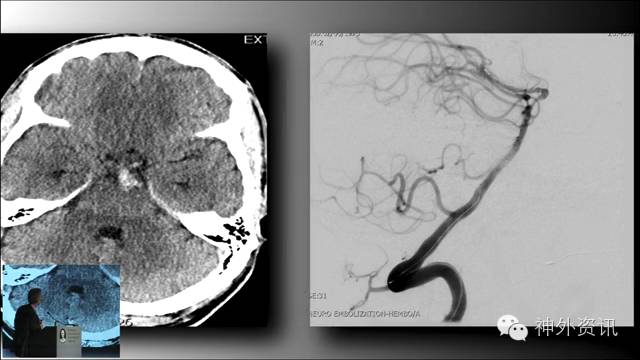

Michael T. Lawton,巴洛神经科学研究所(BNI)主席,精于各种脑血管疾病的治疗,已累及外科治疗4400余例颅内动脉瘤和700余例AVM,发表论文270余篇,参编书籍40余部,著有《Seven Aneurysms: Tenets and Techniques for Clipping》。